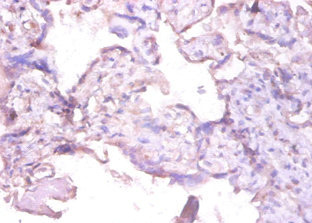

• Immunohistochemistry of paraffin-embedded human spleen tissue using CSB-PA07009A0Rb at dilution of 1:100